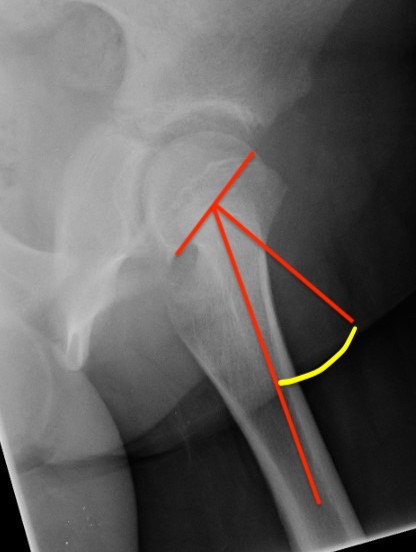

Southwick classification

Southwick Angle / Slip Angle

- epiphyseal-diaphyseal angle on frog leg lateral

- mild <30°

- moderate 30- 50°

- severe >50°

Mild Moderate Severe